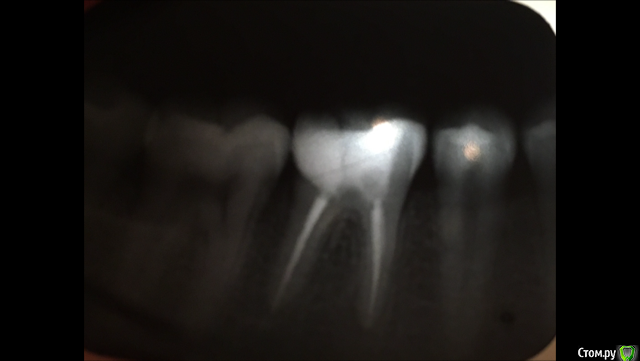

Fyodor333 Опубликовано 25 октября, 2018 Поделиться Опубликовано 25 октября, 2018 Обращаюсь за помощью. 2 дня назад поставили пломбу со стекловолоконным штифтом вместо разрушившейся старой. Третий день есть боли при надкусываи, пару раз за 2 дня при жевании острая боль. Сегодня боли полегче, но снимок все равно сделал, сказали вроде как нормально и отправили. На снимке видно очень много белой области, как будто расширила отверстие больше, чем нужно. Действительно ли все нормально, нету ли перфорации ? Прикрепляю снимки до и после установки новой пломбы. Ссылка на комментарий

Fyodor333 Опубликовано 30 октября, 2018 Автор Поделиться Опубликовано 30 октября, 2018 Обращаюсь за помощью. 2 дня назад поставили пломбу со стекловолоконным штифтом вместо разрушившейся старой. Третий день есть боли при надкусываи, пару раз за 2 дня при жевании острая боль. Сегодня боли полегче, но снимок все равно сделал, сказали вроде как нормально и отправили. На снимке видно очень много белой области, как будто расширила отверстие больше, чем нужно. Действительно ли все нормально, нету ли перфорации ? Прикрепляю снимки до и после установки новой пломбы. Ссылка на комментарий

Павел7809 Опубликовано 31 октября, 2018 Поделиться Опубликовано 31 октября, 2018 Идет 8-й день, боль не прошла, особенно во второй половине дня периодически ноет, отдает в челюсть(((похоже на то , что все таки там перфо.. Ссылка на комментарий

red_butler Опубликовано 1 ноября, 2018 Поделиться Опубликовано 1 ноября, 2018 Перфорации может и нет, но периодонтит есть а дистальной (дальней) стенки нет. Ссылка на комментарий

red_butler Опубликовано 8 ноября, 2018 Поделиться Опубликовано 8 ноября, 2018 А в какой части снимка виден периодонтит у верхушки медиального (правого) корня 5 лет я ходил с запломбированными каналами и зуб ни разу не беспокоил. при хронических заболеваниях жалобы могут отсутствовать Ссылка на комментарий